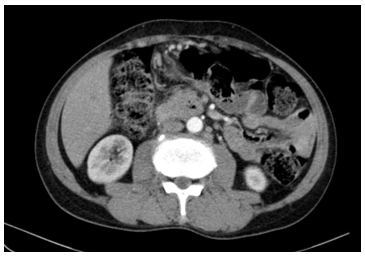

CASE LÂM SÀNG: ĐIỀU TRỊ UNG THƯ ĐẠI TRÀNG GIAI ĐOẠN MUỘN BẰNG HÓA CHẤT KẾT HỢP THUỐC KHÁNG TĂNG SINH MẠCH TẠI TRUNG TÂM YHHN VÀ UNG BƯỚU BỆNH VIỆN BẠCH MAI

CASE LÂM SÀNG: ĐIỀU TRỊ UNG THƯ ĐẠI TRÀNG GIAI ĐOẠN MUỘN BẰNG HÓA CHẤT KẾT HỢP THUỐC KHÁNG TĂNG SINH MẠCH TẠI TRUNG TÂM YHHN VÀ UNG BƯỚU BỆNH VIỆN...

Hiện nay, ung thư đại tràng là một trong những loại ung thư phổ biến nhất trên thế giới cũng như tại Việt Nam. Theo GLOBOCAN 2022, ung thư đại tràng đứng thứ ba trên thế giới về tỷ lệ mắc và đứng thứ...